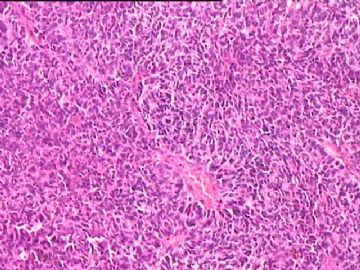

女,34y,头痛一月,右额叶占位:5*5*4cm。囊性区域,4cm。大体:3.5x3x1cm灰白间暗褐色组织一堆,质嫩。临床诊断1:胶质瘤,2:血管母细胞瘤。

• 额叶占位,胶母典型不?图4

图4

胶母

同意胶质母细胞瘤。细胞异型、坏死、核分裂、血管内皮肿胀增生均可见到。

This is certainly a WHO grade IV malignant neoplasm. While most likely a glioblastoma, I would carefully rule out PNET by staining for GFAP and neuronal markers such as synaptophysin, NeuN and NSE. Rarely, PNET may shows marked pleomorphism and indistinguishable from glioblastoma on HE stain.

同意马老师的意见,该肿瘤从形态及年龄来看考虑PNET或GBM,须标记Syn、NSE、S-100、NeuN和GFAP来鉴别。

结合图片细胞形态特点考虑胶质母细胞瘤,组化标记排除其他